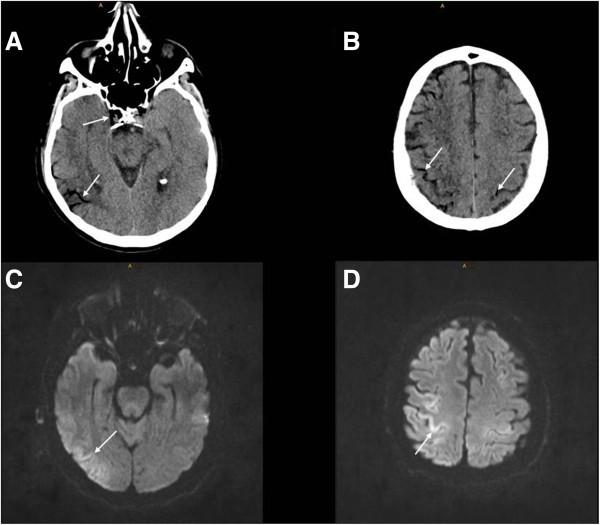

We report a patient with cerebral air embolism after endoscopy of a perineal abscess. Immediate CT imaging confirmed the diagnosis and MRI showed cortically localized areas of restricted diffusion along the gyri. Since hyperbaric oxygenation was not available, moderate hypothermia was applied for neuroprotection.

我们报告一例经会阴脓肿内镜检查后发生脑空气栓塞的患者。立即进行的CT成像确诊了该诊断,MRI显示沿脑回有皮质定位的扩散受限区域。由于无法进行高压氧疗,因此采用中度低温进行神经保护。